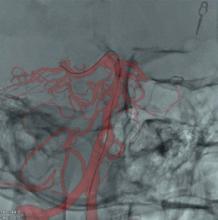

As catheter-based, minimally invasive procedures expand rapidly beyond treatment of the coronary arteries into all areas of the human anatomy, angiography X-ray imaging systems have moved beyond their original purpose of simple vascular imaging. Today, in addition to interventional cardiology, cath labs are frequently shared by numerous specialists, including interventional radiology, interventional oncology, electrophysiology (EP), vascular surgeons and neurology.